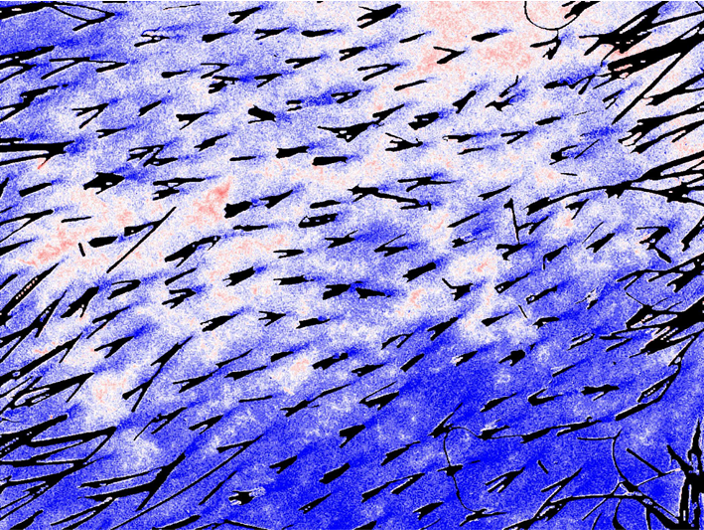

Scalp erythema

Intelligent segmentation excludes hair and analyzes only the scalp, generating a reliable and standardized erythema index.

These developments reinforce protocols related to soothing or anti-inflammatory care.